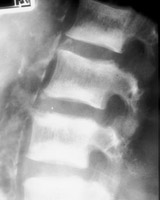

Diagnosis:Chronic renal failure Discussion:Roentgenographic appearance of increased density in the upper and lower zones of the vertebral body in a striated appearance. The pattern was similar to the alternating colors of the rugby players jersey design popular at the time of the description of this entity. Rugger Jersey spine is typically reserved for secondary hyperparathyroidism. References: